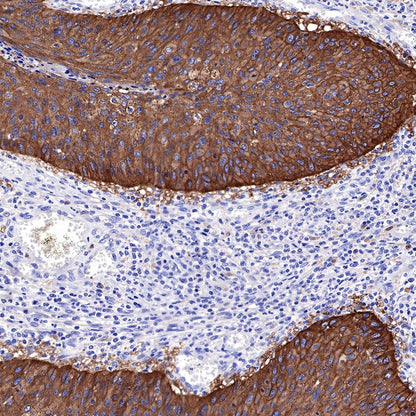

IHC shows positive staining in paraffin-embedded human skin. Anti-EGFR antibody was used at 1/2000 dilution, followed by a HRP Polymer for Mouse & Rabbit IgG (ready to use). Counterstained with hematoxylin. Heat mediated antigen retrieval with Tris/EDTA buffer pH9.0 was performed before commencing with IHC staining protocol.